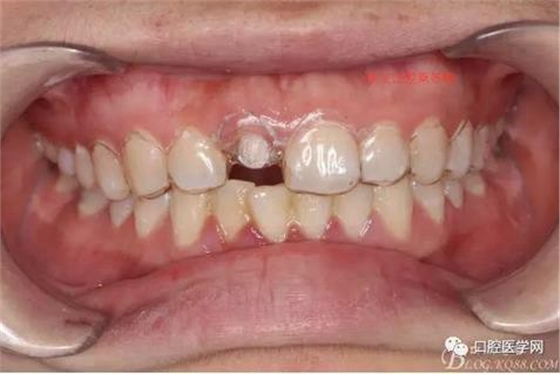

術(shù)前口內(nèi)照,11殘根,唇側(cè)牙齦紅腫,肩臺(tái)在齦下2毫米,舌側(cè)正常.21有被動(dòng)萌出,長(zhǎng)寬比例不協(xié)調(diào)??谇恍l(wèi)生一般,有菌斑。

術(shù)前原有牙冠復(fù)位,牙齦紅腫。